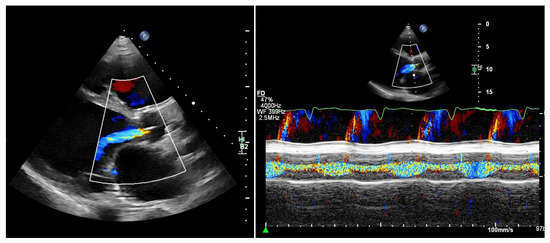

Routine Echocardiographic Assessment in LVAD Patients—A Structured Approach to Acquisition and Interpretation

by Nicolas Merke, Felix Schoenrath, Evgenij Potapov and Jan Knierim

J. Cardiovasc. Dev. Dis. 2026, 13(2), 70; https://doi.org/10.3390/jcdd13020070 - 30 Jan 2026

Durable left ventricular assist devices (LVADs) are an established and highly effective therapy for patients with advanced heart failure. Ongoing technological improvements and structured follow-up programs have significantly enhanced device durability, reduced complications, and improved long-term survival. Consequently, a growing number of patients with LVAD support require long-term outpatient care and increasingly present to both specialized and non-specialized hospitals, including for admissions unrelated to heart failure. In this context, echocardiography plays a central role. It is essential not only for routine follow-up at dedicated LVAD clinics but also for the assessment of cardiac status during inpatient admissions for extracardiac conditions. However, echocardiographic evaluation in LVAD patients is technically demanding and requires a solid understanding of LVAD physiology, device–heart interactions, and the specific hemodynamic conditions of continuous-flow support. Without this knowledge, standard echocardiographic parameters may be misleading. This review provides sonographers and cardiologists with a practical, clinically oriented framework for routine transthoracic echocardiography in patients with durable LVAD support. We summarize key principles of LVAD hemodynamics, discuss interpretation of LVAD console parameters, propose a standardized imaging protocol, and outline a structured approach to common echocardiographic findings in routine ambulatory and inpatient settings. Full article